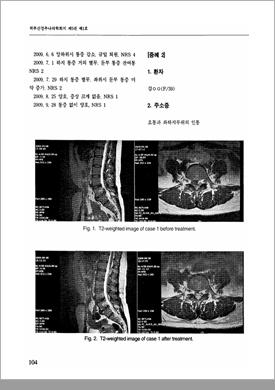

2010년 발표한 논문을 통해 척추수술실패증후군 (FBSS)과 같은 중증 허리디스크 질환도 한방치료만으로 치료가 가능하며,

수술과 달리 재발 위험이 낮다는 치료 결과를 입증하였습니다.

2010년 발표한 논문을 통해 심한 허리통증으로 요추 4/5번 추간판탈출증 진단을 받은 환자에게

추나요법을 비롯한 한방치료로 통증이 크게 호전되었다는 치료 결과를 입증하였습니다.

2009년 발표한 척추신경추나의학회

허리디스크 요통 논문

(이진혁 원장)